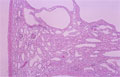

- (1)Autosomal-recessive polycystic kidney disease (childhood)

Macroscopic view; The kidney is enlarged. On cut section, numerous small cysts give the kidney a sponge-like appearance. As kidney function in utero is decreased this results is lower than normal production of amniotic fluid (oligohydramnios) which can have further consequences on fetal development (Lung hypoplasia, Potter sequence in the neonate)